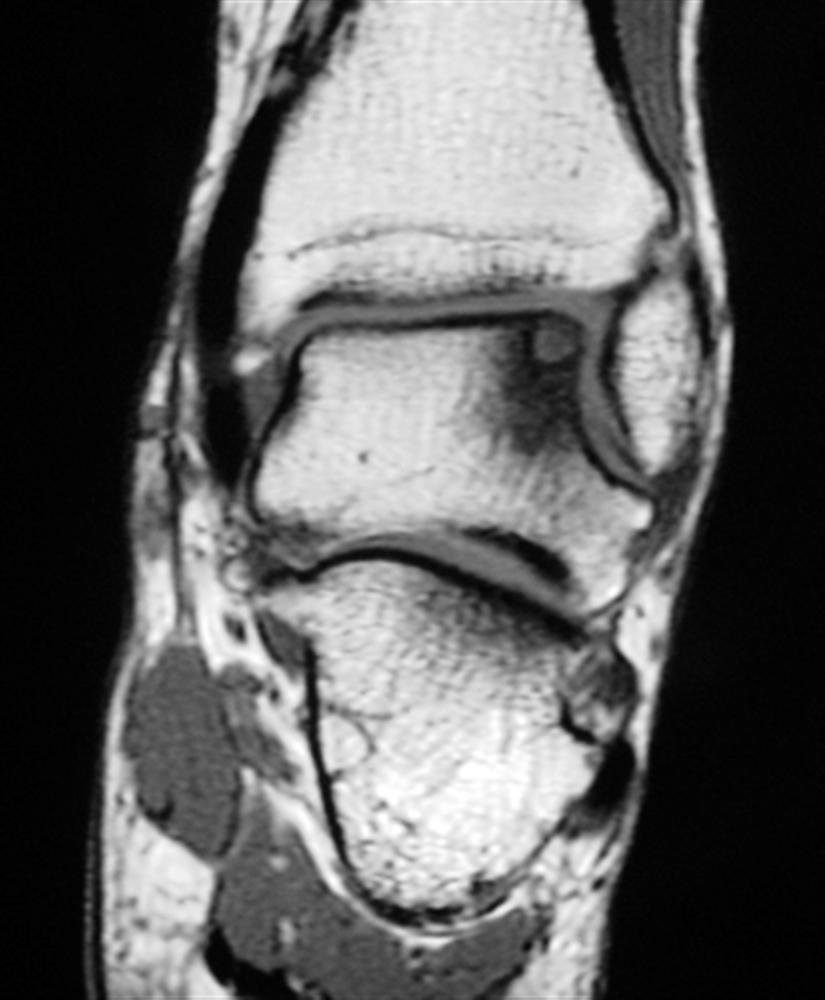

Figure 2 from Osteochondritis dissecans of the talus. Semantic Scholar Talus Bone Ocd An osteochondral lesion of the talus (olt) is an area of abnormal, damaged cartilage and bone on the top of the talus bone (the lower bone of the ankle. It can occur in all age groups. Osteochondritis dissecans (ocd) of the talus is a subchondral bone pathology that presents as an osteochondral lesion of the talar dome with. Symptomatic osteochondral. Talus Bone Ocd.